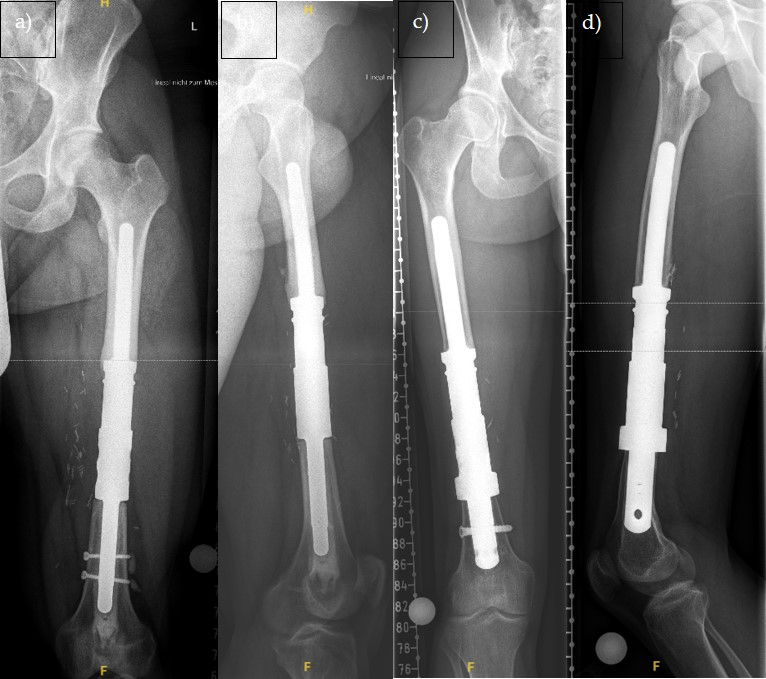

- Femur: 16.4 cm (SD = 4.6);

- Tibia: 14.8 cm (SD = 3.1);

- Humerus: 8.6 cm (SD = 1.0).